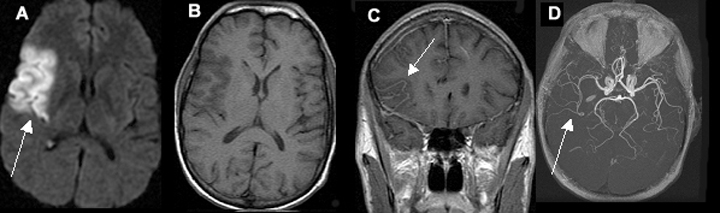

Acute One Day Old Infarction Involving the Right Middle Cerebral Artery (MCA) Territory

A. Diffusion weighted image shows area of infarct as bright signal.

B. T1 image shows no evidence of blood in the area of infarct (blood would appear as white).

C. Post contrast coronal image shows vascular enhancement in the area of infarct.

D. MR angiography shows right middle cerebral artery branches to be narrower in calibre, as compared to left.